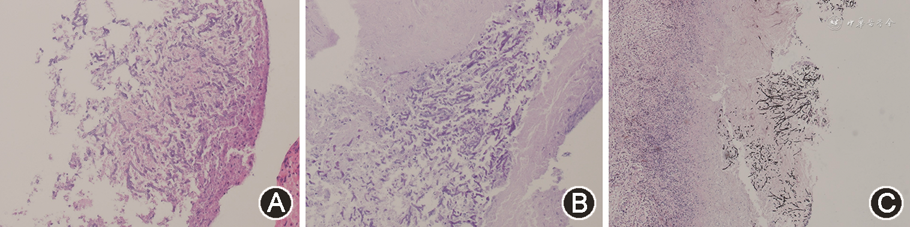

T1+:对比度增强T1加权成像

出院后患者未有抽搐发作,2021年12月复查头颅MRI示:左侧额叶靶形T1低信号、T2高信号,增强后环形强化,周围多发大片状T1低信号、T2高信号(图1B)。考虑颅内病灶为脓肿可能,再次收入病房,完善原发病评估:血常规、血肌酐无明显异常,血清白蛋白23 g/L,24 h尿蛋白4.49 g;抗SSA、抗Ro52抗体阳性,IgG 5.87 g/L,C3、C4正常。血清(1,3)-β-D葡聚糖试验(G试验)、半乳甘露聚糖试验(GM试验)均阴性。腰椎穿刺脑脊液压力为175 mmH2O,脑脊液常规、生化、细胞学、细菌、真菌涂片培养及脑脊液第二代测序(next-generation sequencing,NGS)均为阴性。PET/CT:左额叶白质区囊性结节,仅囊壁有轻度代谢活性,最大标准摄取值7.7,伴周围大片水肿。治疗上继续予泼尼松、羟氯喹、左乙拉西坦,加以罗氏芬2 g 1次/12 h静脉点滴17 d,复查头颅增强MRI未见变化(图1C)。多学科会诊建议开颅行手术切除活组织检查(活检),术前抗感染改为美罗培南2 g 1次/8 h+万古霉素1 g 1次/12 h。2022年1月25日全身麻醉后行神经导航下左额叶脓肿切除术,组织培养提示烟曲霉菌(图2,3),NGS回报烟曲霉菌、细环病毒、人类疱疹病毒5型,病理检查(图4)示:坏死物、真菌(曲菌)菌丝及肉芽组织,周边极少许水肿的神经组织。特染结果:过碘酸雪夫染色(periodic acid-Schiff staining)阳性,六胺银染色阳性。抗感染方案遂改为伏立康唑0.2 g 1次/12 h联合美罗培南2 g 1次/8 h。患者未再出现发热及神经系统症状,原发病好转后于2022年2月24日出院。出院后继续口服伏立康唑片0.2 g 1次/12 h,于2022年3月21日及2022年4月4日规律复诊,诉无癫痫再发,复查MRI示术后改变,术区类圆形信号影呈缩小趋势,边缘少许强化,未见环形强化(图1D、E)。患者已于2022年8月20停用伏立康唑。